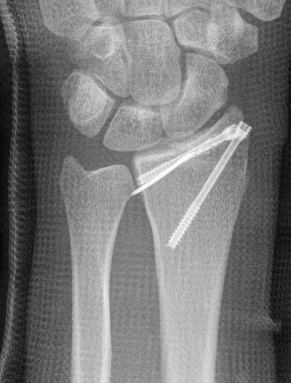

Xray

Dorsal radiocarpal dislocation with radial styloid fracture

Radial styloid

- percutaneus screws +/- radial styloid plate